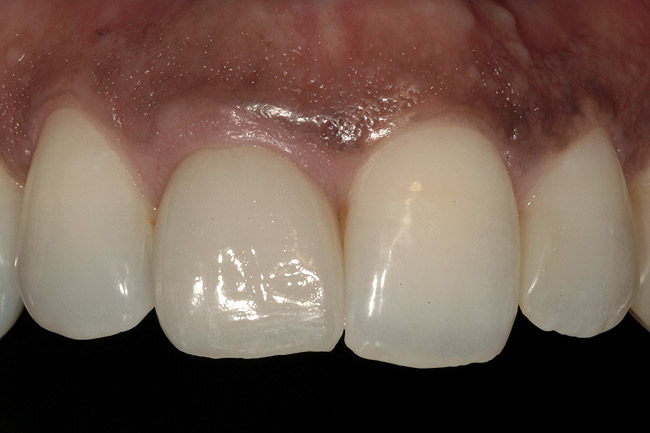

From a clinical perspective, the primary challenge was the development of an esthetic emergence of the dental implant-supported crown restoration. Maintenance of the soft-tissue dimensions, therefore, was critical to the treatment success. In an effort to optimally maintain the ridge form, a connective tissue graft harvested from the palate39,40 was placed over the collagen membrane to augment the soft tissues. Then, the buccal flap was advanced to achieve primary closure. Postoperative healing proceeded uneventfully. The overlying soft tissue exhibited rapid clinical closure and healed with minimal evidence of the surgical procedure. The clinical outcome was also consistent with development of the desired ridge form. Cone-beam computed tomography imaging revealed an alveolar ridge form that was optimal for implant placement at 5 months post-treatment. The radiographic density of the augmented region was similar to the adjacent native bone, with no discernable interface between native and apparent new bone, consistent with integration and remodeling. Surgical re-entry for implant placement revealed the optimal ridge form (Figure 6 ). The implant was allowed to integrate for 5 months prior to the healing abutment placement and interim restoration. The overcontoured soft tissues enabled surgical sculpting to achieve the desired contour for the restorative emergence. A highly acceptable esthetic result was achieved. With preservation of the marginal and papillary gingival contours (Figure 7 and Figure 8 ); the radiographic presentation was consistent with normal bone remodeling and implant integration.

Figure 7  Esthetic result achieved at the provisional stage of restoration.

Figure 7

Figure 8  Marginal and papillary gingival contours were well preserved using this technique.

Figure 8